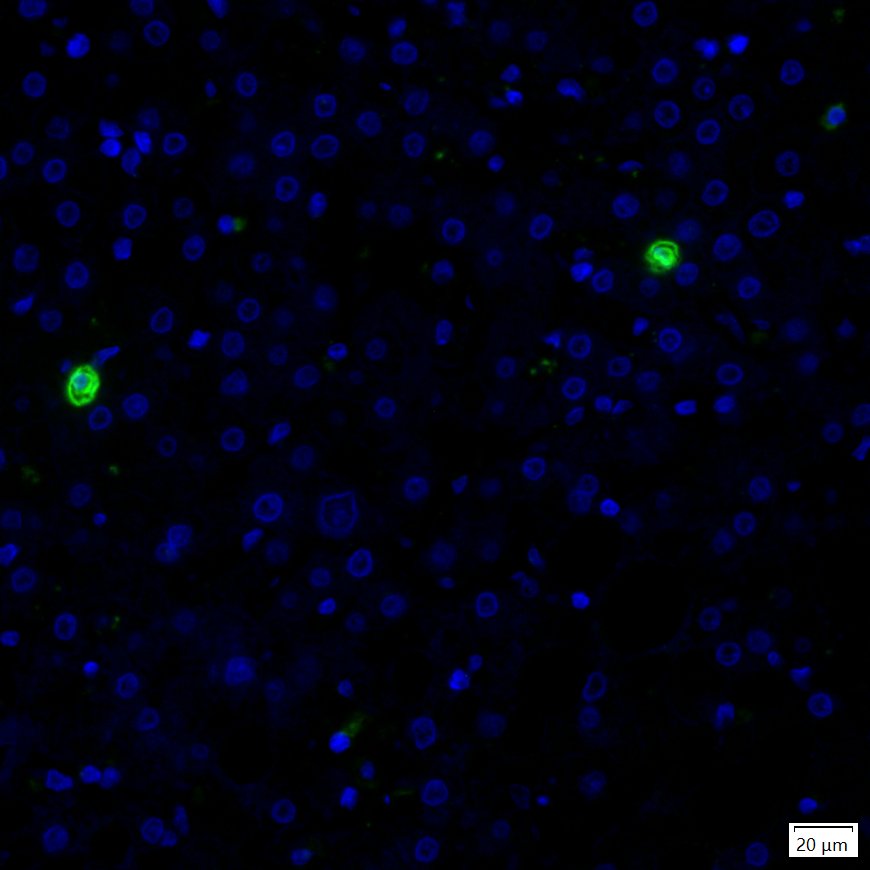

IRS003_9.jpg Fig9: mIHC analysis of human tonsil tissue (Formalin/PFA-fixed paraffin-embedded sections) with Rabbit anti-CD20 antibody (IRS003) at 1/100 dilution. The immunostaining was performed with the IRISKitCmTSA Kit (900808). Heat mediated antigen retrieval with Tris-EDTA buffer (pH 9.0) for 30 mins at 95℃. DAPI (blue) was used as a nuclear counter stain. Image acquisition was performed with Olympus VS200 Slide Scanner.